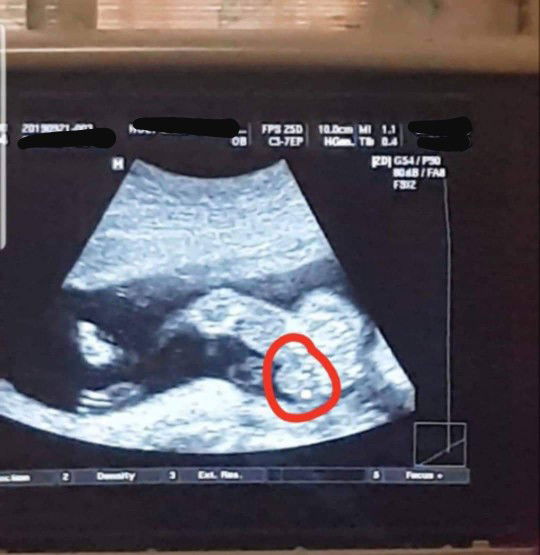

Hello mommies.. nag pa ultrasound ako kanina kasi excited na ako.. pero hndi pa masabi ni ob kung boy o girl kasi matambok.. parang scrotum/ ball sac daw nakikita nya o pwedeng matambok lang ung pempem.. pero naisip ko naman masyado ata matambok kung pempem un ni baby kasi kung ikukumpara halos kasize na ng tuhod nya e.. kaya feeling ko tuloy boy sya at itlog nya ung nakaumbok na yan sa pic ? un nga lang hndi kita ung lawit, kaya confused ako baka girl nga siya. ? ano po sa tingin nyo? Hehe 19weeks po now si baby..i-ultrasound po ulit ako next month ? Thanks po.. ?